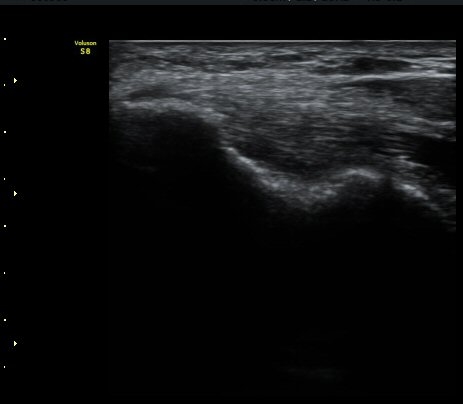

ÃÊÀ½ÆÄ °Ë»ç

³»»ó°ú¿¡¼­ ¼Õ¸ñ±¼°î°Ç Á¾´Ü¸é°Ë»ç»ó ³»¤µ¾Æ°ú ÇÇÁú°ñÀÇ ºÒ±ÔÄ¢º¯È­¿Í ÈûÁÙ³» ¿¬°á¼º

¼Ò½Ç ¹× Àü¹ÝÀûÀÎ Àú¿¡ÄÚ ºÎÁ¾ÀÌ °üÂûµÈ´Ù(±×¸² 1, 2, 3). ±¼°î°Ç ÀϺδ Á¤»óÀûÀÎ °í¿¡ÄÚ

¼¶À¯ ¾ç»óÀ¸·Î °üÂûµÈ´Ù(±×¸² 4). ÈûÁ٠Ⱦ´Ü¸é °Ë»ç¿¡¼­µµ °Ç³» ¿¬°á¼º ¼Ò½Ç°ú Àú¿¡ÄÚ

º¯È­°¡ °üÂûµÈ´Ù(±×¸² 5).  ÃÊÀ½ÆÄÀ¯µµÇÏ ÁÖ»ç ½Ã ÁÖ»ç¾×ÀÌ °Ç³»¿¡¼­ ÀÚÀ¯·Ó°Ô ÆÛÁ®¼­

°ÇÀÇ ½ÉÇÑ ÆÄ¿­À» º¸¿©ÁØ´Ù(÷ºÎ ÆÄÀÏ µ¿¿µ»ó 1).